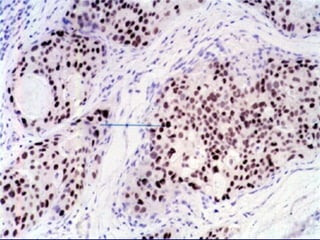

Immunohistochemistry Ag-Ab complexes The bound Ab is then visualized, using another Ab and a dye complex such as diaminobenzidine.

Immunohistochemistry Ag-Ab complexesThe bound Ab is then visualized, using another Ab and a dye complex such as diaminobenzidine.